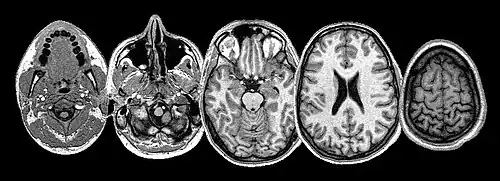

Neuroimaging sheds light on the seat of suffering

Many brain structures and physiological processes are involved in suffering (particularly the anterior insula and cingulate cortex, both implicated in nociceptive and empathic pain).[29] Various hypotheses try to account for the experience of suffering. One of these, the pain overlap theory[30] takes note, thanks to neuroimaging studies, that the cingulate cortex fires up when the brain feels suffering from experimentally induced social distress, as well as physical pain. The theory proposes therefore that physical pain and social pain (i.e. two radically differing kinds of suffering) share a common phenomenological and neurological basis.